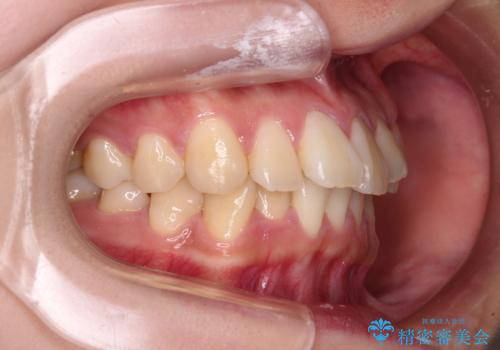

- 前歯の捻れを気にして来院された患者様です。

上顎前歯が捻れて前方に飛び出しており、下顎前歯もそれに沿うようにデコボコとなっていました。

IPR(歯と歯の間を削る処置)によりスペースを獲得して下顎前歯のデコボコを改善し、上顎前歯は下顎前歯と接する位置にまで引っ込めるように設定し、インビザラインにて矯正治療を行うこととしました。